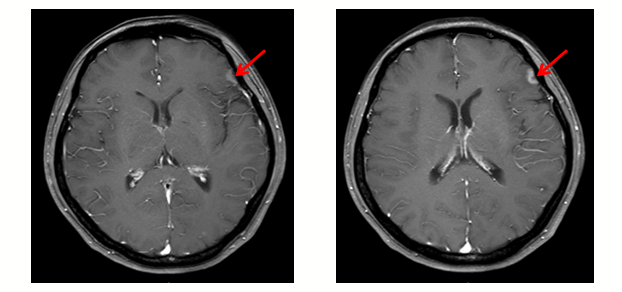

2020年7月,全胸CT显示未见明显转移瘤,脑MR显示左侧额叶新发异常信号结节影,考虑脑转移瘤。在系统治疗方案吡咯替尼+卡培他滨的基础上,对脑转移灶进行立体定向放疗(SRT)。最佳疗效为病情稳定(SD),PFS为2+月。

图3 2020年7月脑MR检查结果